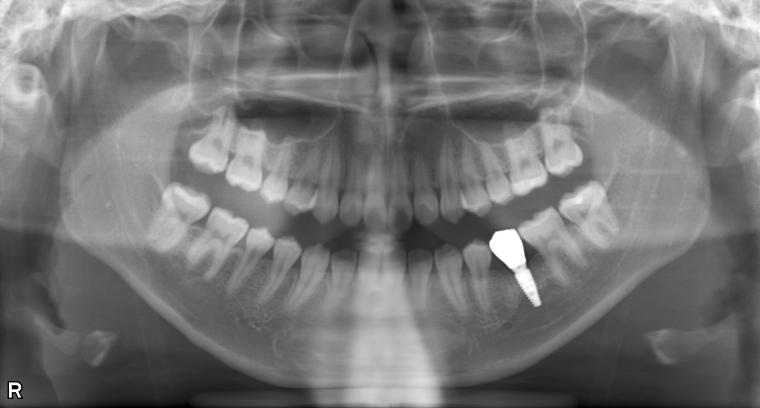

AFTER

19歳女性/下1本欠損/インプラント埋込手術

他の歯の健康を考えマウスピース矯正で歯列を整えてからインプラントを1本埋込しました。

現在も定期検診で拝見させていただいてます。